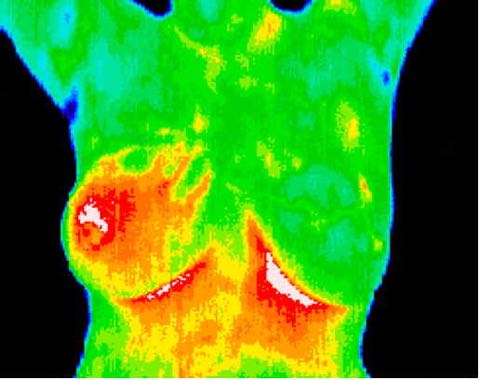

Inflammatory cancer, asymptomatic and unsuspected